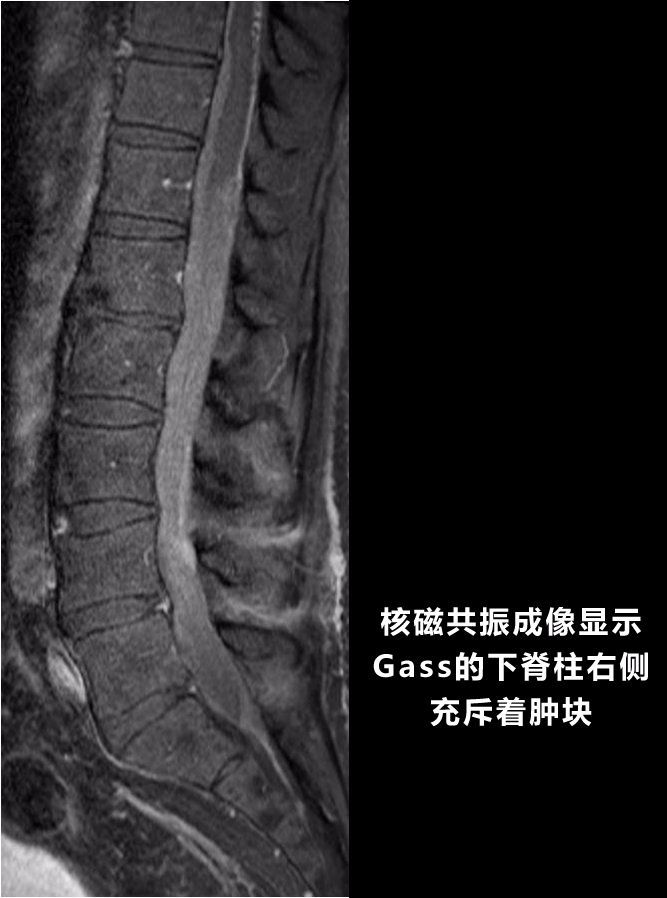

纽约时报在2016年曾报道过一起可怕的案例。为了从中风后恢复,Jim Gass在墨西哥、阿根廷等地接受了干细胞治疗,花了近30万美元。不久后,医生在他的脊柱中发现了巨大的肿块。

图/New York Times

“整个肿块充满了血液组织,当我想要取片的时候,它开始流血。”Jim Gass的医生说,“我从来没见过这种东西。”

化验显示,肿块由异常的、原代细胞组成,而且正在极为迅速地生长。令人震惊的是,这些细胞并非来自Jim Gass本人,而是另有其人。这正是干细胞注射治疗的结果。

Jim Gass图/New York Times

中风后,尽管Jim Gass左半边身体几乎瘫痪,但他还能自主生活。而现在,除了右手还能活动,他的脖子以下全数瘫痪。医生根本不知道如何阻止他体内的外来细胞继续生长。